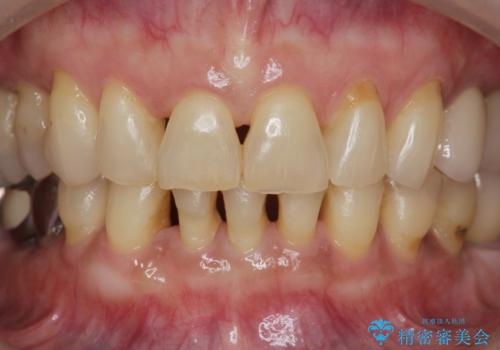

前歯のすれ違いによる歯周病を矯正治療で改善

矯正治療を行うことで、歯を削ったり(ブリッジ)、手術の必要(インプラント)なく機能を欠損部位を無くし機能回復を達成することができました。